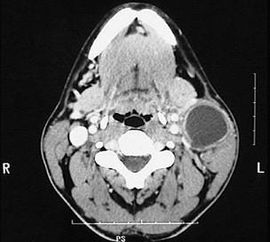

先天性第一鰓裂囊腫廈瘺管臨床少見,易誤診、誤治。影像學(xué)檢查是術(shù)前確診的重要依據(jù);充分的術(shù)前準(zhǔn)備和合理的手術(shù)方案是該病治愈的關(guān)鍵,完整切除囊腫度瘺管是避免復(fù)發(fā)的重要措施。